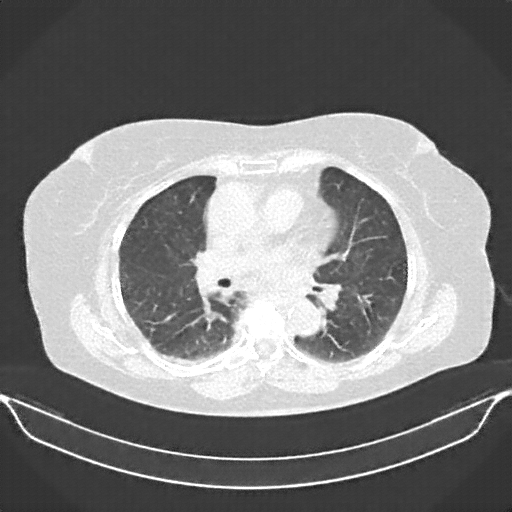

Original NATIVE CT scan (input)

Full window (WL 1023.5, WW 4095 β†’ Low βˆ’1024, High +3071)

Lung window (WL -600, WW 1500 β†’ Low βˆ’1350, High +150)

Mediastinum window (WL 40, WW 400 β†’ Low βˆ’160, High +240)